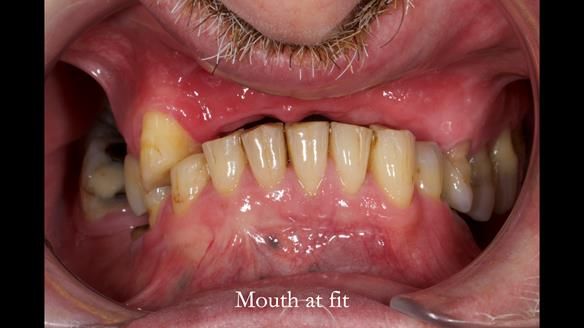

Keith’s case was one of the most challenging and rewarding cases I’ve treated this year. This 64 year old man presented with ill-fitting acrylic partial dentures that lacked stability, retention, and aesthetics. They constantly broke. He had lost the upper front teeth in a road traffic accident in his early 20s. The unopposed teeth had erupted, taking up space. After careful planning, we made a durable, metal-based upper partial denture/splint to address his dental concerns. He loved the outcome.

1. Denture design: A custom cobalt-chromium framework was Scandinavian-designed to maximise stability, protect the remaining teeth, and allow for future additions if needed.

2. Onlay preparations: Composite onlays were fitted for his upper left premolars to repair these teeth and support the new denture.

3. Definitive alginate impression in custom tray: Used to ensure a well-fitting RPD.

4. Keith’s outcome: The final denture not only improved Keith’s bite, chewing function, and facial aesthetics but also protected his remaining teeth from further damage.

What makes this case really interesting?

Keith’s denture incorporated a Duracetal shell clasp on upper right first premolar (Myerson), which are designed to be virtually visible, providing a more aesthetic solution while enhancing patient comfort. The Scandinavian-inspired approach, based in modern removable prosthodontic techniques, ensured the denture was not only durable but also visually pleasing. Additionally, the design was carefully planned to allow for future modifications, ensuring that if Keith loses additional teeth, the denture can be adapted rather than replaced entirely.

I also used the Dahl concept to re-establish the occlusion upon fitting the RPD, which helped to intrude the lower left canine without needing to grind it too much.